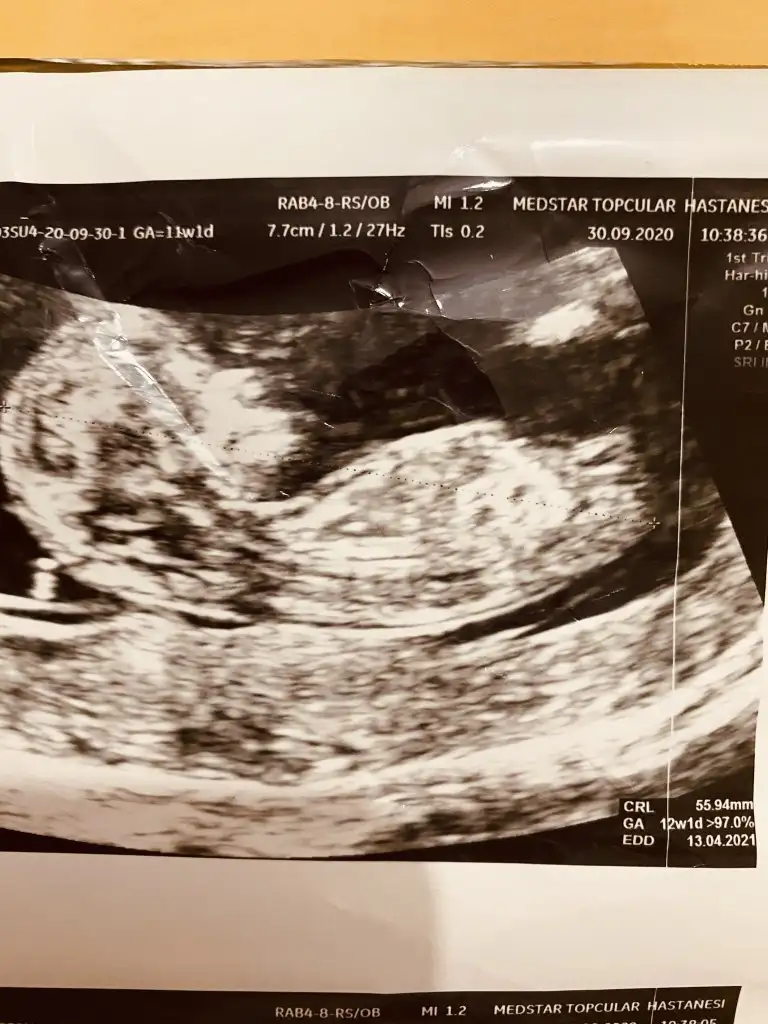

Tamam teşekkür ederim haftaya tekrar atarımİkiside kız görünüyor ama bu haftalar yanitir siz 11 12 13 haftalar paylasin

Nubu çok karışık net varsa paylasinCanım biz eşimle baya inceledik. Bizimkisi baya örnek kız bebek nubu vermiş ultrasonda. Ama sen daha tecrübelisin sen ne diyorsun nubuna